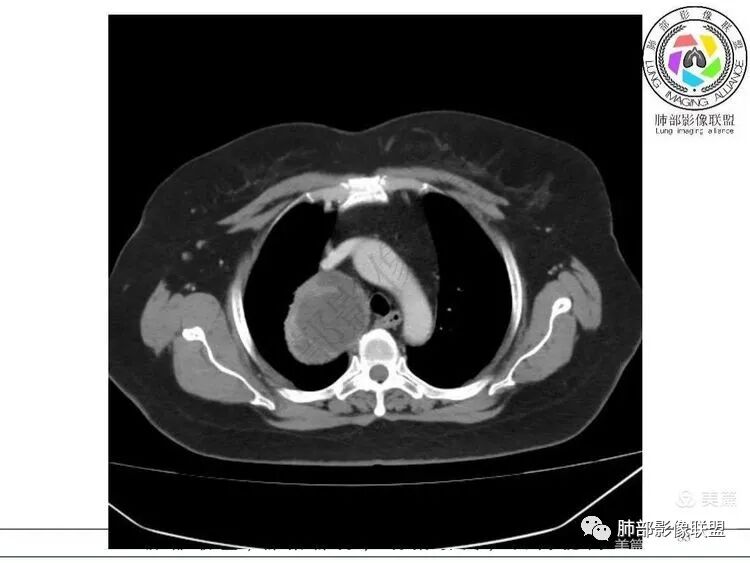

1. 右上胸廓入口区类椭圆形块影,边界清楚光整,纵向“嵌顿”于颈根部及上纵隔,向上推移右锁骨下动静脉,向外下方推移上肺胸膜及肺组织(肺血管、支气管),向前推移上腔静脉,界限清楚。

2. 块影不均匀轻度强化,可见较均匀实性区及液性密度区,未见积气、囊壁样结构、钙化或脂肪密度。可疑部分肋间动脉分支进入。

肿块部位、密度以及强化特点聚焦于良性神经鞘瘤及孤立性纤维瘤。

3.而“A/B”区密度特点以及上下径较大更支持神经鞘瘤,尽管这不属于好发部位。